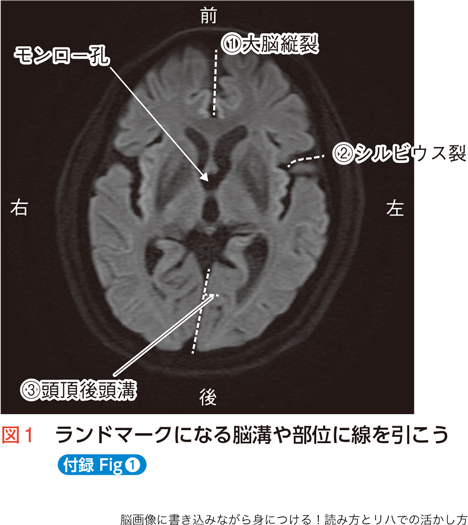

- 先輩PT:そうだね。でもいきなり内包を探しに行ってはいけないよ。まずはいつも通りランドマークになる脳溝や部位に線を引いていこう(図1)。

- 先輩PT:まずは大脳縦裂(①)だね。中央部分には間脳があるから、前方部分と後方部分に分けて線を引いてね。次は大脳皮質の外側の脳溝だけど、これまで見えていた中心溝はこのレベルでは見えなくなっていることが多いんだ。頭頂葉の代わりに側頭葉が見えるようになっているので、前頭葉と側頭葉の境目にあたる…。

- 学生PT:シルビウス裂ですね!

- 先輩PT:そう、シルビウス裂(②)に線を引こう。とても太い隙間だから見つけやすいね。

- 若手PT:あと側頭葉と後頭葉の境目は、後方内側面にある頭頂後頭溝(③)で側脳室レベルと一緒ね。